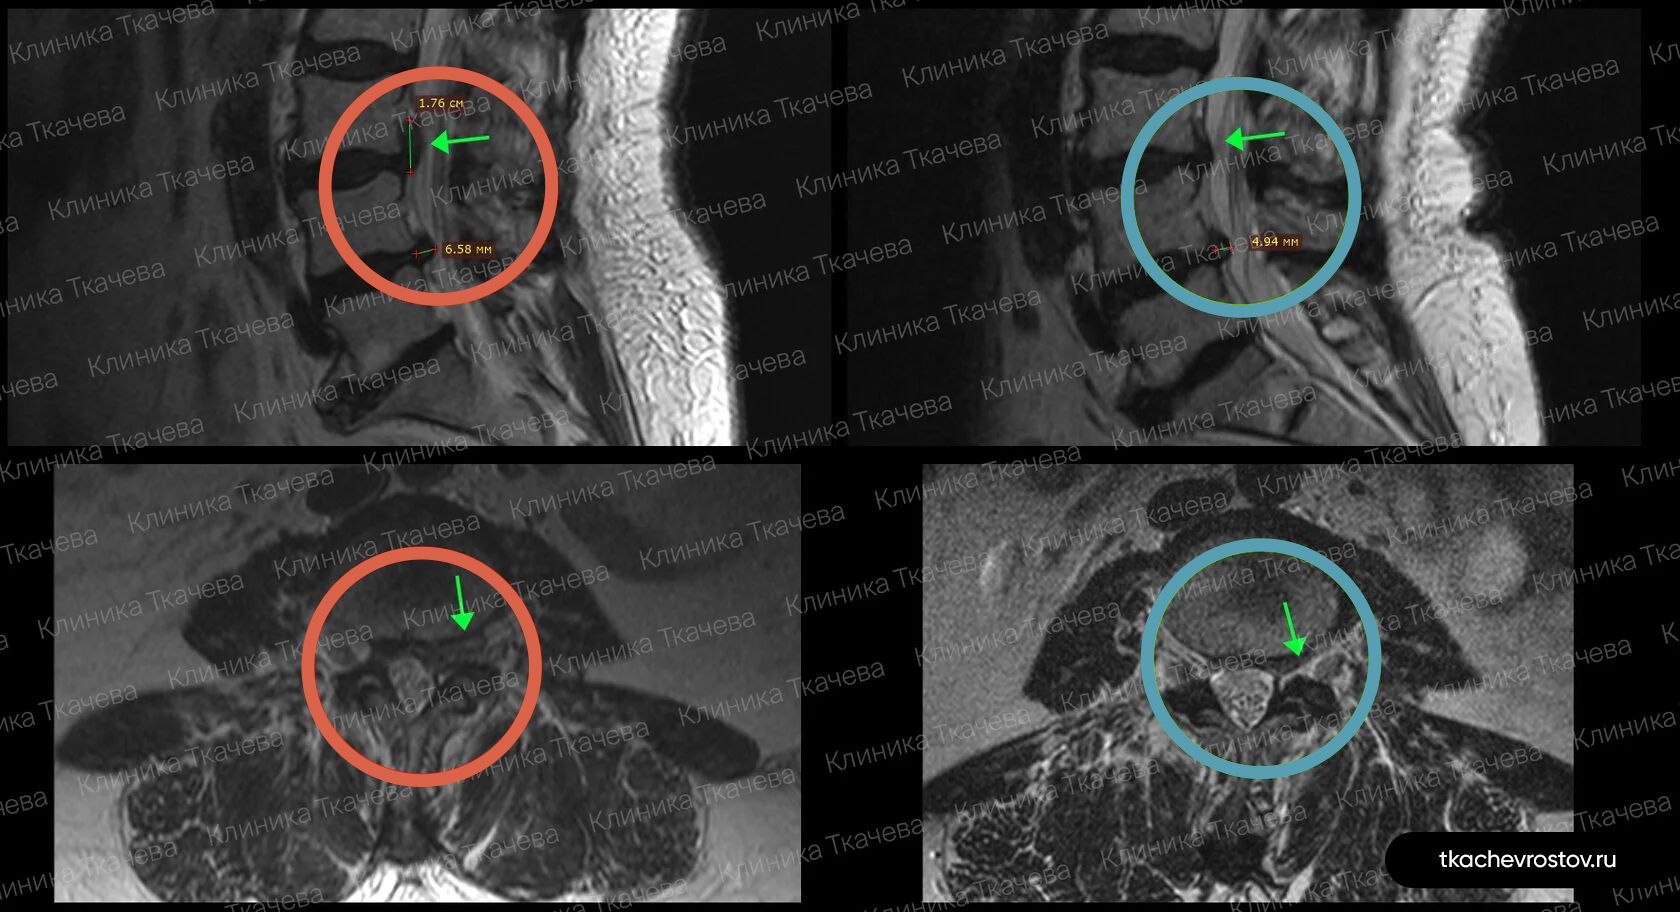

Грыжа в поясничном отделе L5-S1

Мужчина. Секвестрированная грыжа в поясничном отделе L5-S1 1.3 x 3.2 см. Невыносимая боль, хромота и критическое снижение нейропроводимости обеих ног. Никаких альтернатив кроме операции не предлагалось.

ДО:

-

Упражнения с физиотерапевтом и блокады

- Длительная отрицательная динамика

- Невыносимая боль

- Хромота и онемение пальцев ног

- Критическое снижение нейропроводимости обеих ног

- Потеря трудоспособности и ограничение жизнедеятельности

ПОСЛЕ 1 курса:

✓ Наступила полная резорбция грыжи

✓ Наступило улучшения общего состояния

✓ Регрессировали боль и онемение в ноге и пальцах

Пациент прошел 1 курс лечения (12 дней).